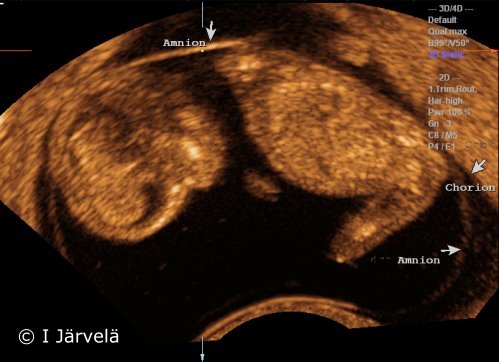

Amnion and chorion (ultrasound scan)

Pregnancy week 11.

Pictures: Ilkka Järvelä; text: Dimitrios Scordas